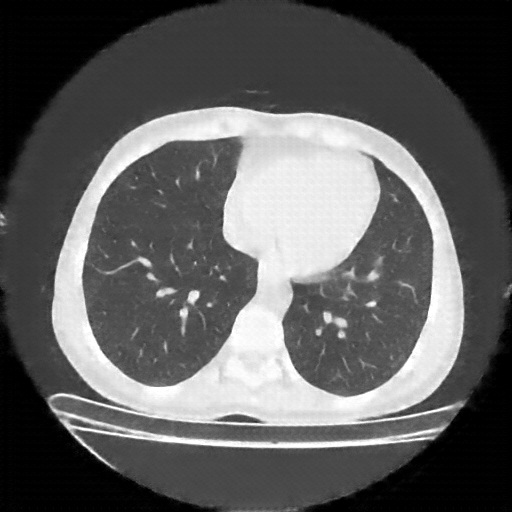

Generated VENOUS CT scan (A→B translation)

No window - Raw intensity values

Lung window (WL -600, WW 1500 β†’ Low βˆ’1350, High +150)

Mediastinum window (WL 40, WW 400 β†’ Low βˆ’160, High +240)